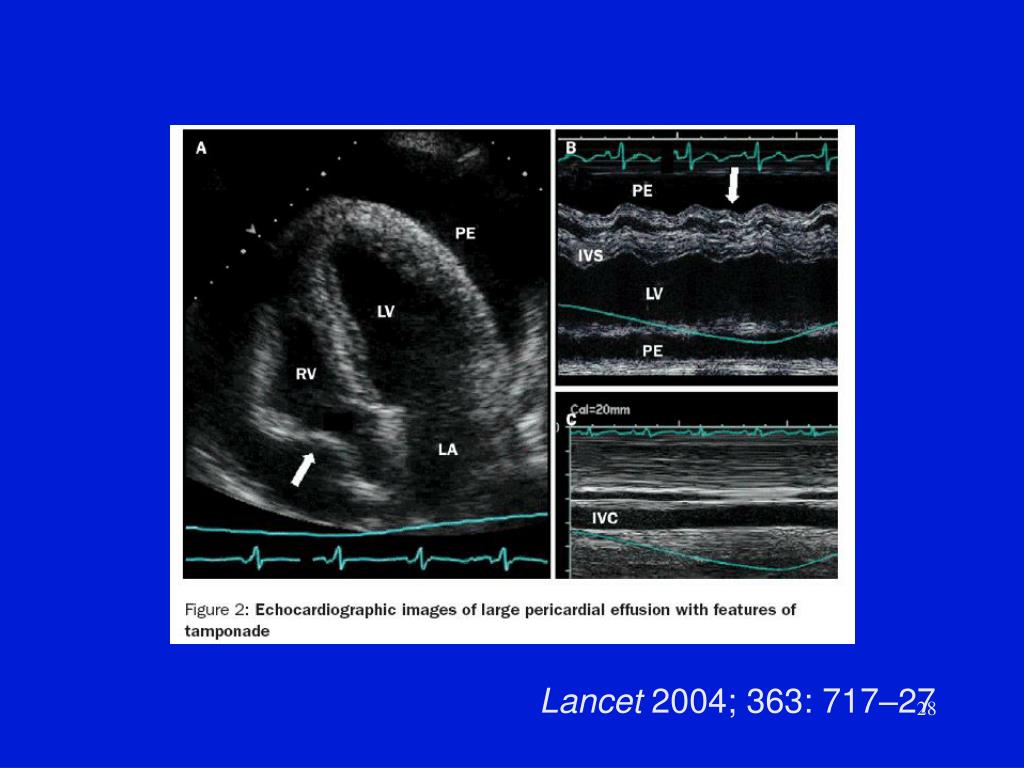

25. Tamponade • Echocardiography • Compression of RV and RA in diastole • Can have localized effuison with localized compression of one chamber (RA,LV) • Effusion post cardiac surgery • Differentiate other causes of low cardiac output • Cardiac catheterization- definitive • Measure pressures- chamber and pericardial equal, and all elevated.

27. Lancet 2004; 363: 717–27